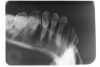

The occlusal image, as seen in Figure 3, is very useful in determining the buccolingual extension of pathologic conditions and provides additional information as to the extent and displacement of fractures of the mandible and maxilla. Occlusal radiographic images also aid in localizing unerupted teeth, retained roots, foreign bodies, and calculi in the submandibular and sublingual salivary glands and ducts. It should be noted that when imaging soft tissues, exposure time needs to be appropriately reduced.

Figure 3 - Occlusal Images

Figure 3